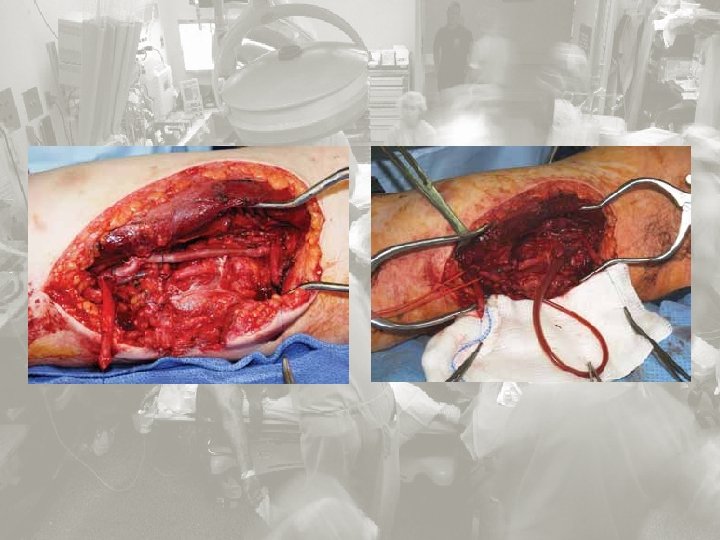

Wskazania do „damage control surgery”: Ciężkie obrażenia jamy brzusznej – kl. piersiowej Złamania miednicy z rozległym krwiakiem zaotrzewnowym Znacznego stopnia uszkodzenia wątroby Obrażenia penetrujące dwunastnicy i trzustki Znaczne uszkodzenia (naczyń, narządów, jelit ) Niska rezerwa fizjologiczna Temperatura < 35ºC p. H < 7, 2 Kwas mlekowy> 5 mmol/L Czas protrombinowy < 50% Ciśnienie skurczowe < 90 przez okres >1 hour Krwawienie z utratą 4000 ml krwi Koagulopatia. Rozsiane krwawienia nie wywołane urazem mechanicznym. Damage control surgery JESÚS MÁRQUEZ ROJAS 1, GERARDO BLANCO FERNÁNDEZ 2, DIEGO LÓPEZ GUERRA 2 1 Servicio de Cirugía General y del Aparato Digestivo, Hospital San Pedro de Alcántara, Cáceres, Spain. 2 Servicio de Cirugía General y del Aparato Digestivo, Hospital Infanta Cristina, Badajoz, Spain.

Damage control in the injured patient Jeremy M Hsu , Tam N Pham Department of Surgery, University of Washington, Harborview Medical Center,